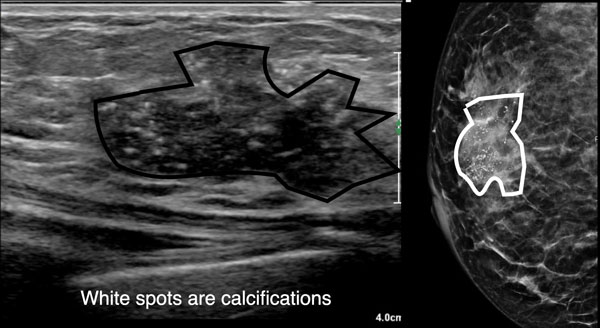

Đây là hình ảnh của một phụ nữ 50 tuổi tự sờ thấy khối u ở vú.

Hãy mô tả các dấu hiệu siêu âm, sau đó tiếp tục đọc.

Các dấu hiệu siêu âm bao gồm:

- Khối giảm âm với hình dạng không đều

- Bờ không rõ ràng, vừa có góc cạnh vừa mờ nhạt

- Các chấm tăng âm nhỏ, tương ứng với các vôi hóa

- Không có bóng cản phía sau hoặc tăng âm phía sau

Các vôi hóa này cũng được quan sát thấy trên hình ảnh nhũ ảnh.

Vùng trắng trên nhũ ảnh chính là khối u.